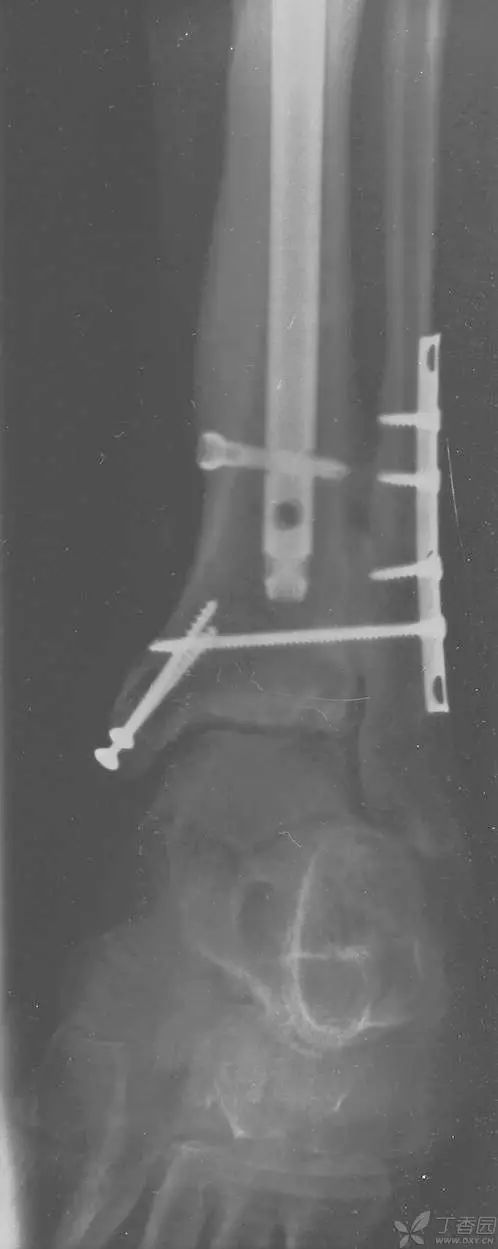

病例二[9]

33 岁男性,车祸多发伤。左踝严重污染,几乎环形创口,胫骨远端 20 cm 缺损

游离骨块生理盐水灌洗,保持湿润,4 小时内紧急手术。术中对创口和游离骨块各用 12L 生理盐水灌洗,彻底清创。外固定支架固定,创口松散地缝合

原计划 48 小时再次灌洗,因身体情况不稳定,10 天后再次进手术室清创灌洗,方法如前;48 小时后进行了第三次灌洗,然后进行了内固定,闭合创口。

3 个月后创口无感染迹象,骨折处无压痛

6 个月后,骨折线模糊,独立行走

18 个月恢复工作